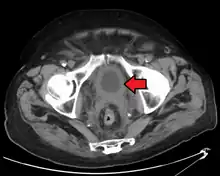

-

Bladder wall thickening due to cancer -